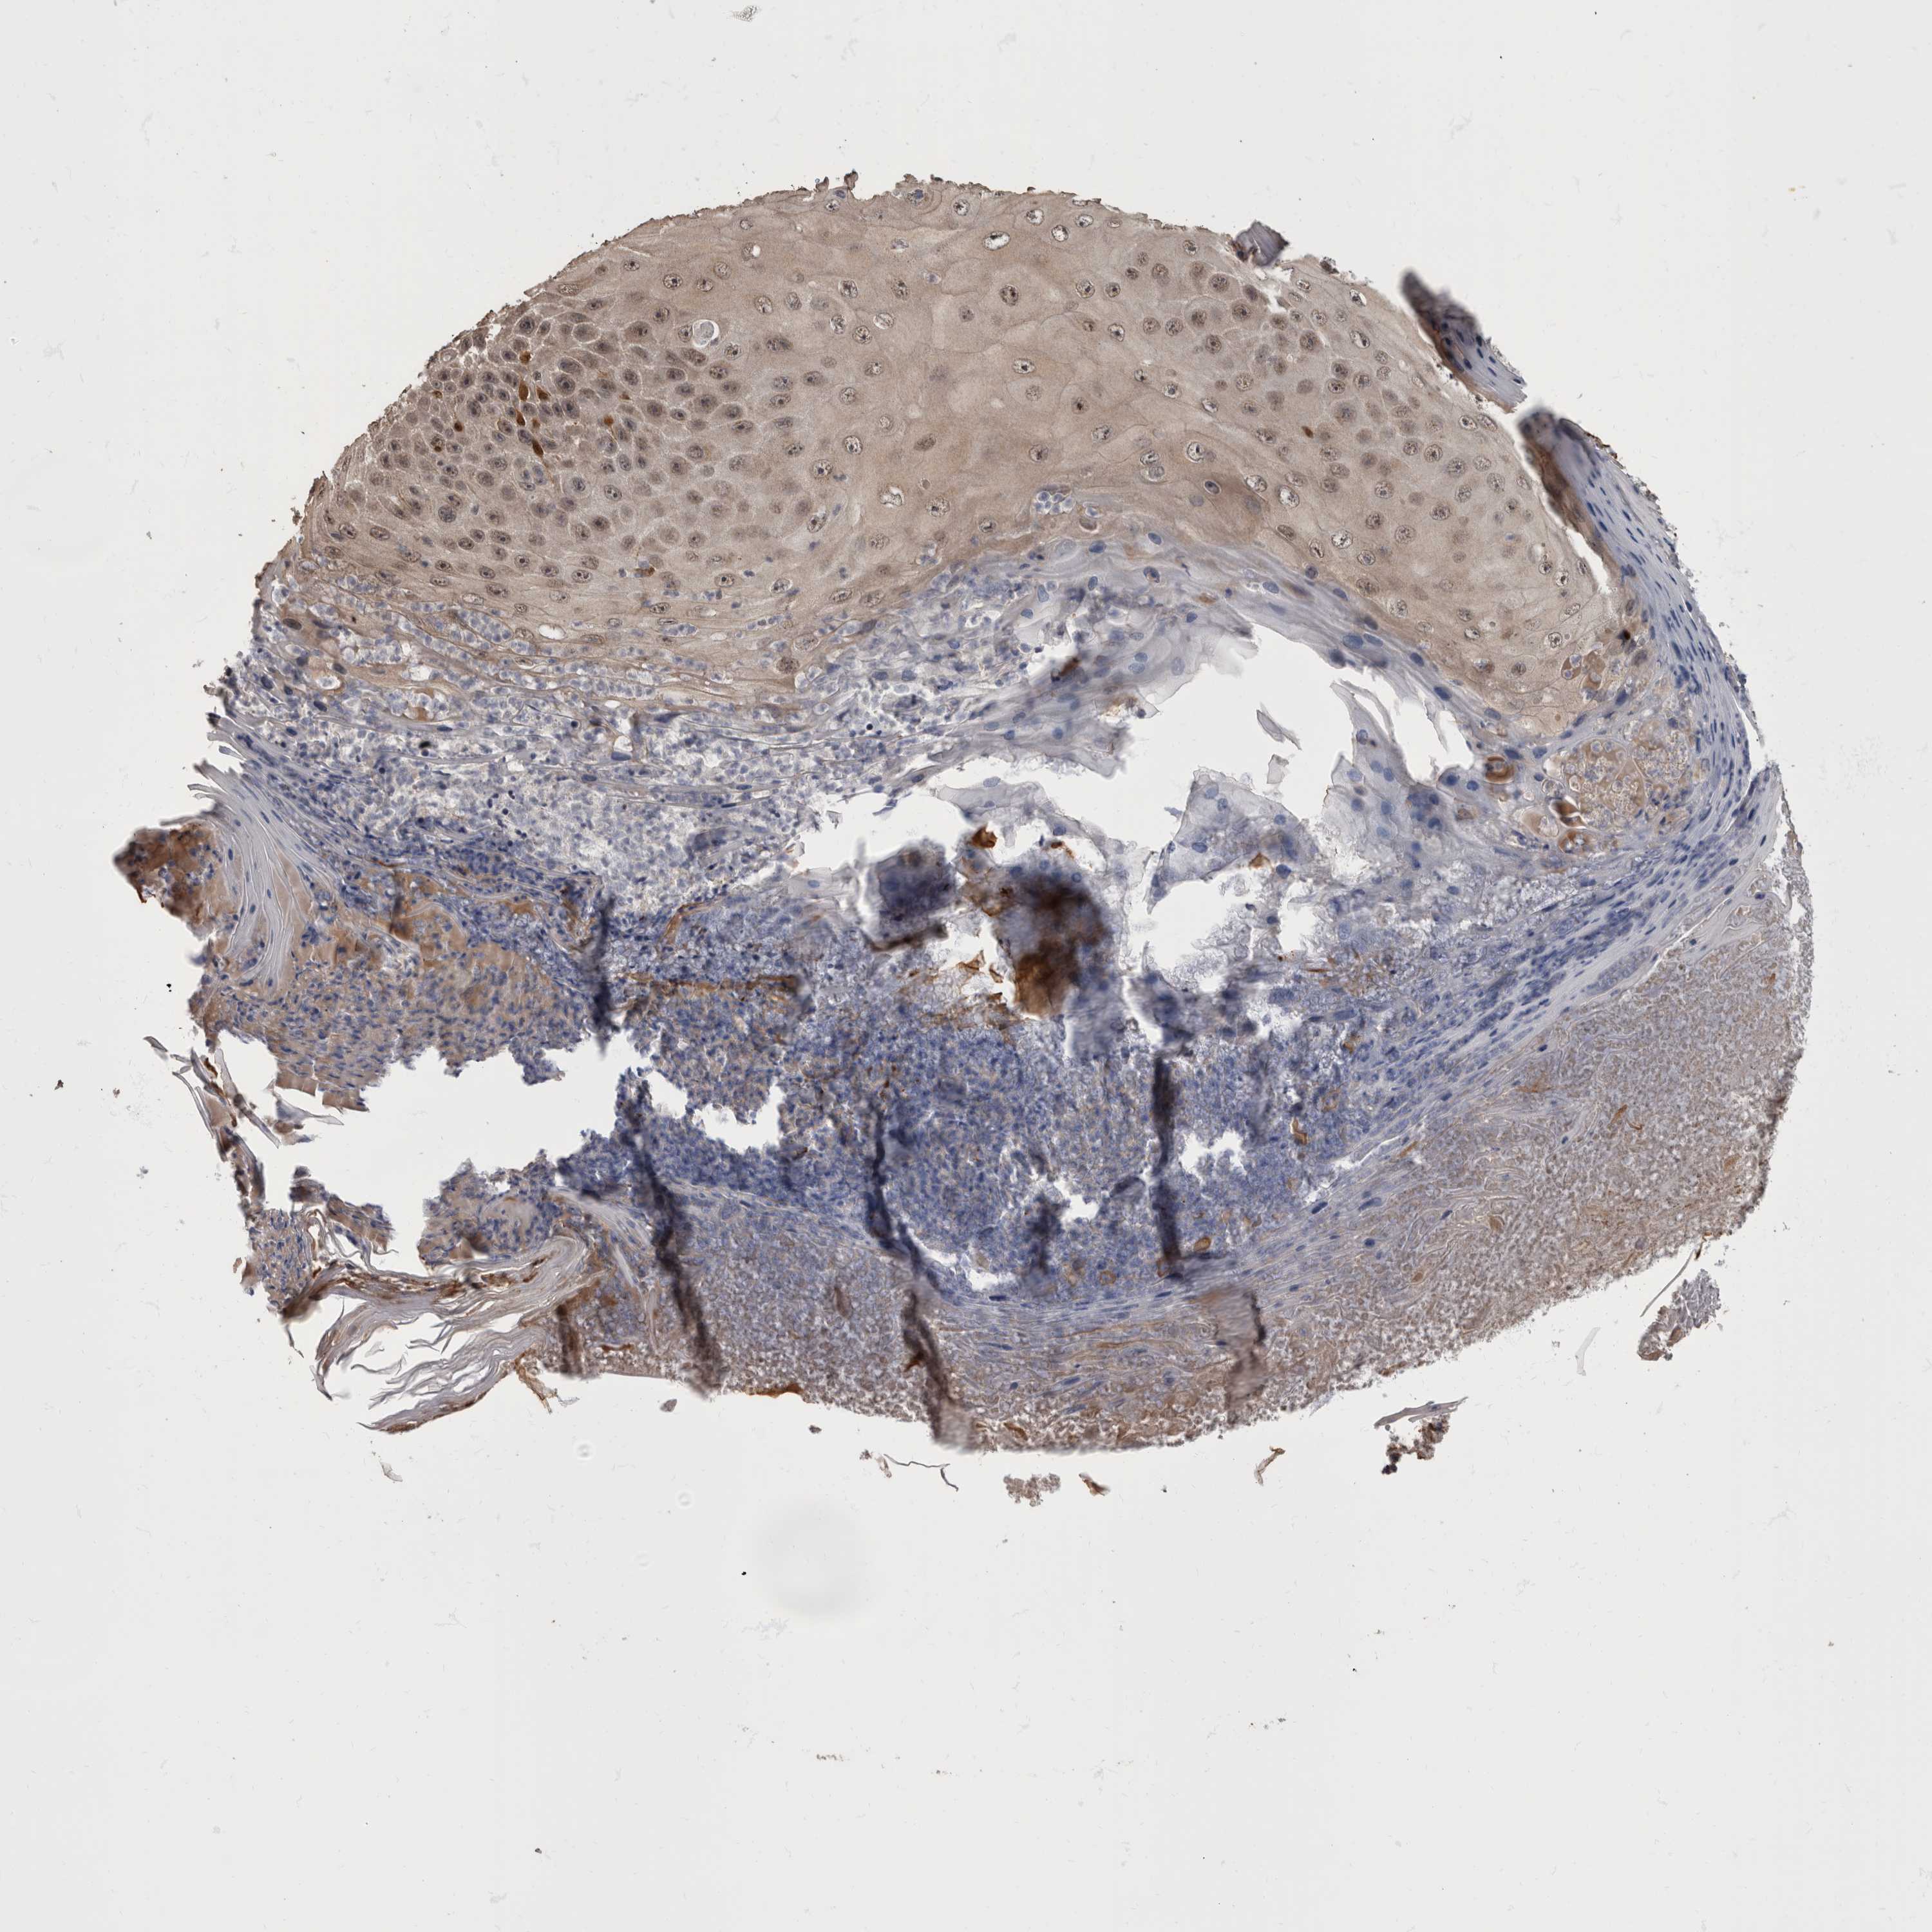

SKIN CANCER - Protein expressioni

A mouse-over function shows sample information and annotation data. Click on an image to view it in a full screen mode. Samples can be filtered based on level of antibody staining by selecting one or several of the following categories: high, medium, low and not detected. The assay and annotation is described here.

Antibody stainingi

Antibody staining in the annotated cell types in the current human tissue is reported as not detected, low, medium, or high, based on conventional immunohistochemistry profiling in selected tissues. This score is based on the combination of the staining intensity and fraction of stained cells.

Each image is clickable and will lead to virtual microscopy that enables deeper exploration of all samples and also displays staining intensity scores, fraction scores and subcellular localization as well as patient and tissue information for each sample.

Antibody HPA026441

Antibody CAB013090

Staining

High

Medium

Low

Not detected

Intensity

Strong

Moderate

Weak

Negative

Quantity

>75%

75%-25%

<25%

None

Location

Nuclear

Cytoplasmic/membranous

Cytoplasmic/membranous,nuclear

Basal cell carcinoma